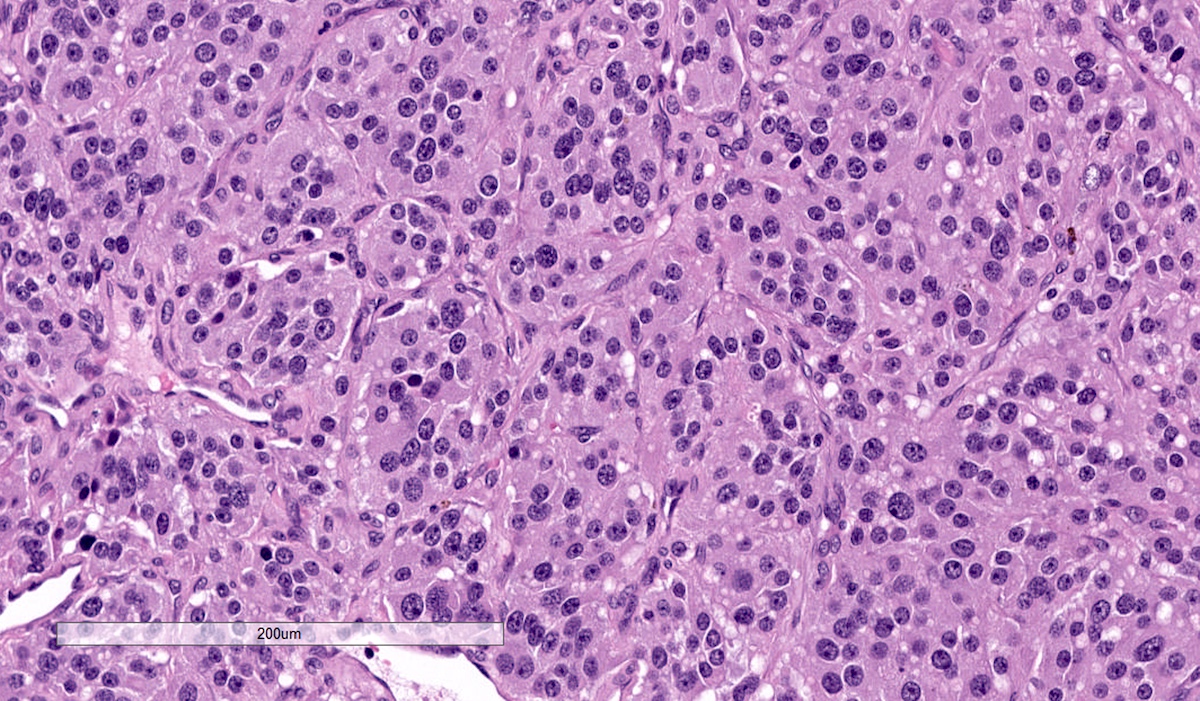

Microscopic (histologic) description

- Prevailing histologic pattern: epithelioid chief cells arranged in distinctive clusters / nests (zellballen pattern), separated by prominent fibrovascular stroma (J Clin Med 2018;7:280)

- Trabecular pattern: ribbons or cords of epithelioid cells divided by fibrous bands

- Other patterns: pseudorosette, angioma-like, spindled and sclerosing

- Chief cells: round, oval to polygonal cells with abundant granular basophilic, eosinophilic or amphophilic cytoplasm (Surg Pathol Clin 2019;12:951)

- Intracytoplasmic hyaline globules may be present in sympathoadrenal paragangliomas

- Giant multinucleated cells and bizarre cells can be present (Srp Arh Celok Lek 2002;130:7)

- Rarely, elongated and spindle shaped cells with a sarcomatoid appearance may be found

- Scattered ganglion cells can be seen

- May have nuclear atypia

- May have dysmorphic vessels, melanin-like pigment (neuromelanin) (pigmented paraganglioma), amyloid, abundant stroma and osseous metaplasia (Diagn Pathol 2012;7:77, Hum Pathol 1992;23:33)

- No or rare mitotic figures except in highly aggressive rapidly proliferating lesions

- May have focal chronic inflammatory infiltrate

- Necrosis is unusual except in patients who have undergone preoperative tumor embolization

Microscopic (histologic) images

Contributed by Luvy Delfin, M.D. and Sylvia L. Asa, M.D., Ph.D.